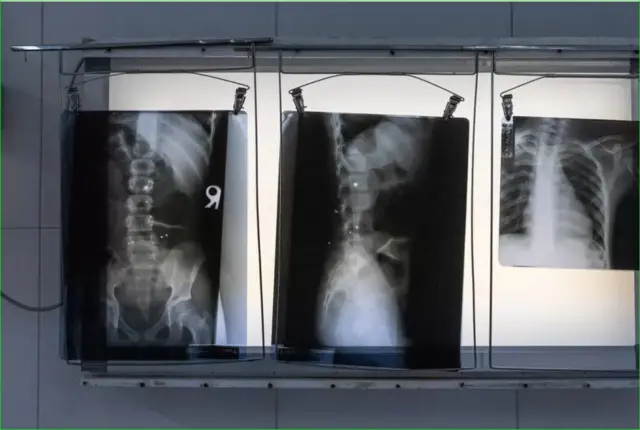

عمران اکنون ۱۳ ساله است او یک خط زخم جراحی طولانی در جلوی نیم تنه و یک جای زخم در سمت چپ شکم و بافت زخم بیشتری در قسمت پایین کمرش دارد. چرههای (ترکش) گلوله در داخل بدنش مانده است - از جمله یک قطعه بزرگ که در ستون فقراتش جا گرفته است. او به آرامی به جای زخمهای روی شکم و کمرش اشاره کرد و گفت: «دویدن باعث دردم میشود و در شکمم احساس درد میکنم. در زمستان نیز درد بیشتری احساس میکنم و وقتی تابستان میشود راحت میشوم.»

بلال ۱۱ ساله است. بر اثر اصابت گلولهای که به فاصله میلیمتری از چشم چپ به او اصابت کرده، زخمی بر روی صورتش دیده میشود و زخمی بر روی شانهاش است که گلوله دیگری به او اصابت کرده و ترکش گلولهای در استخوانش باقی مانده است. او گفت که وقتی زیاد از دستش استفاده میکند بازویش درد میگیرد و جای زخم روی صورتش یادآور دائمی است از اینکه چقدر به مرگ نزدیک شده است.

خانواده فقیری است، و پسران از زمانی که یک دهه پیش از بیمارستان ترخیص شدهاند دسترسی محدودی به مراقبتهای پزشکی داشتهاند. آنها اخیراً برای معاینه پزشکی که توسط بیبیسی ترتیب داده شده بود، به بیمارستان تروما در شهر لشکرگاه، در فاصله حدود شش ساعت رانندگی از روستا، رفتند. اشعه ایکس نشان داد که قطعات گلوله هنوز در بدن آنها باقی مانده است. این اولین باری بود که پسرها آن گلولهها را میدیدند. پزشکان گفتند که ترکشها را از بدن عمران نمیتوان امن و بیخطر خارج کرد، بنابراین او باید با آنها زندگی کند. جراح گفت: «او خوش شانس است که زنده مانده است».